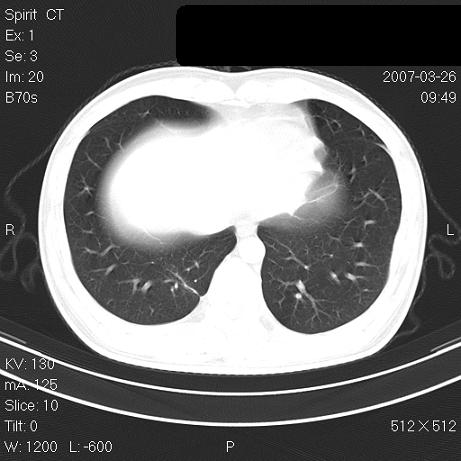

治疗后2周复查,请讨论

结合以前的ct片,还是考虑肺挫伤,吸收多了。

支持:创伤性湿肺。现肺挫裂伤(出血 积气)大部分吸收。建议继续治疗!

结合以前的ct片,支持创伤性湿肺。现大部分吸收。

支持:创伤性湿肺、肺挫裂伤。现肺挫裂伤(出血、渗出、液气腔)大部分吸收。建议继续治疗!

支持:创伤性湿肺、肺挫裂伤。现肺挫裂伤(出血、渗出、液气腔)大部分吸收.

结合老片支持创伤性湿肺、肺挫裂伤。

经治疗后病灶明显吸收,考虑创伤性湿肺、肺挫裂伤